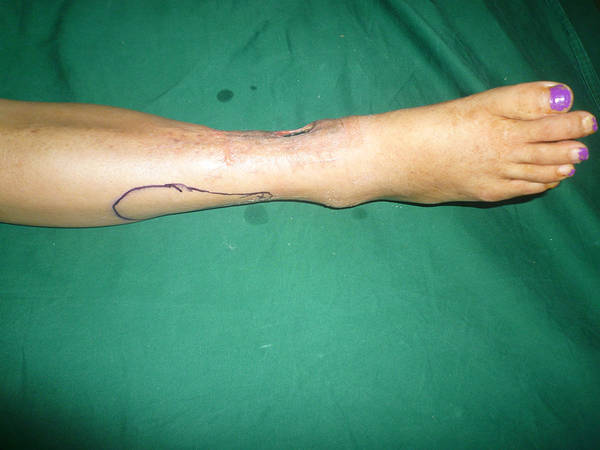

[组织瓣] 改良外踝上皮瓣的再次改良

看看吧这个皮瓣有什么不一样的地方?

以腓动脉穿支为蒂,皮瓣只靠穿支供血,改良的地方是将皮瓣 通过皮下隧道部的分皮肤保留在原位。这样蒂部宽松,平整,又不浪费皮肤,减少手术创伤。

改良中的改良

蒂部不带皮肤,皮下隧道

利用外踝上8cm点穿支血管,向远端游离,紧贴骨膜下剥离,池老师,对不对

1蒂部不带皮肤了2皮下隧道=外观更美。